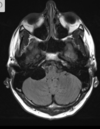

Q

A

Esclerose mesial temporal

Observe a perda de volume, que indica atrofia e causa aumento secundário do corno temporal do ventrículo lateral.

O sinal alto no hipocampo reflete a gliose.